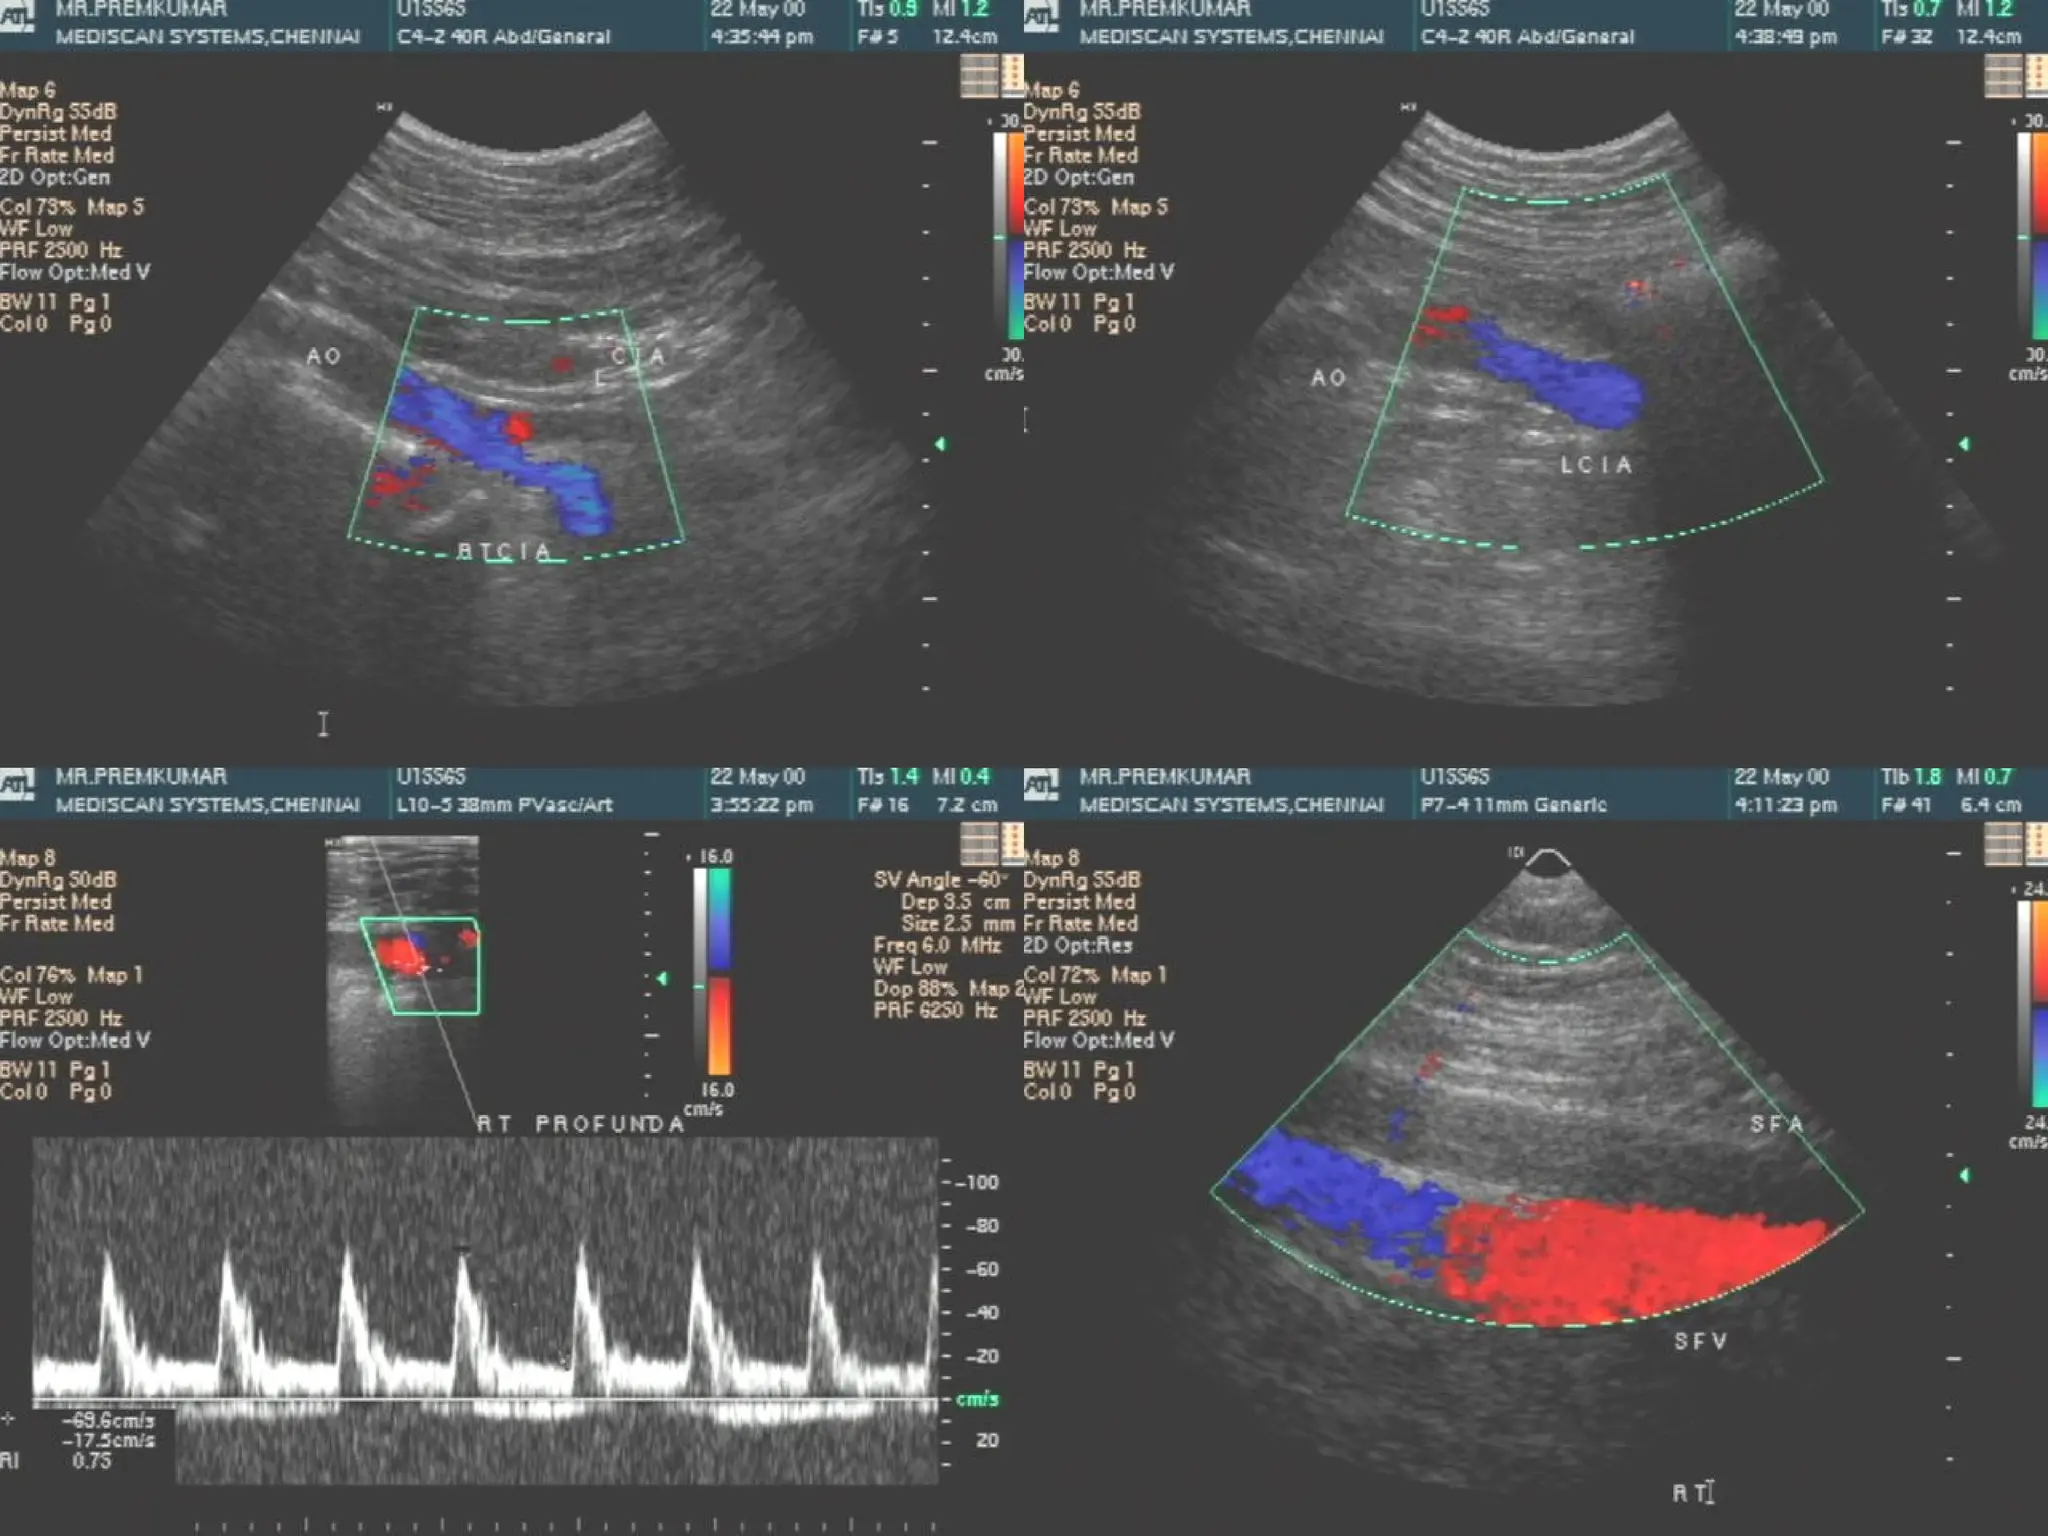

Case II

 Mr. PM – 48 Yrs

Mr. PM – 48 Yrs

 Smoker– 10 Yrs

Smoker– 10 Yrs

 Pain in left foot since 3 weeks

Pain in left foot since 3 weeks

Segmental pressures

170

100

70

30

Brachial

- 140

- 150

AAI – 0.67 AAI – 0.21

USG findings

 Right side : -

Right side : -



Total occlusion of right superficial femoral

artery.

Collateral seen joining the popliteal artery with

reduced forward flow distally.

 Left side : -

Left side : -

Total occlusion of external iliac artery and lower

limb arteries.

 Normal flow seen in aorta, both common iliac

Normal flow seen in aorta, both common iliac

artery and external iliac artery on right side.

 Normal flow seen in right common femoral artery

Normal flow seen in right common femoral artery

and profunda femoris.